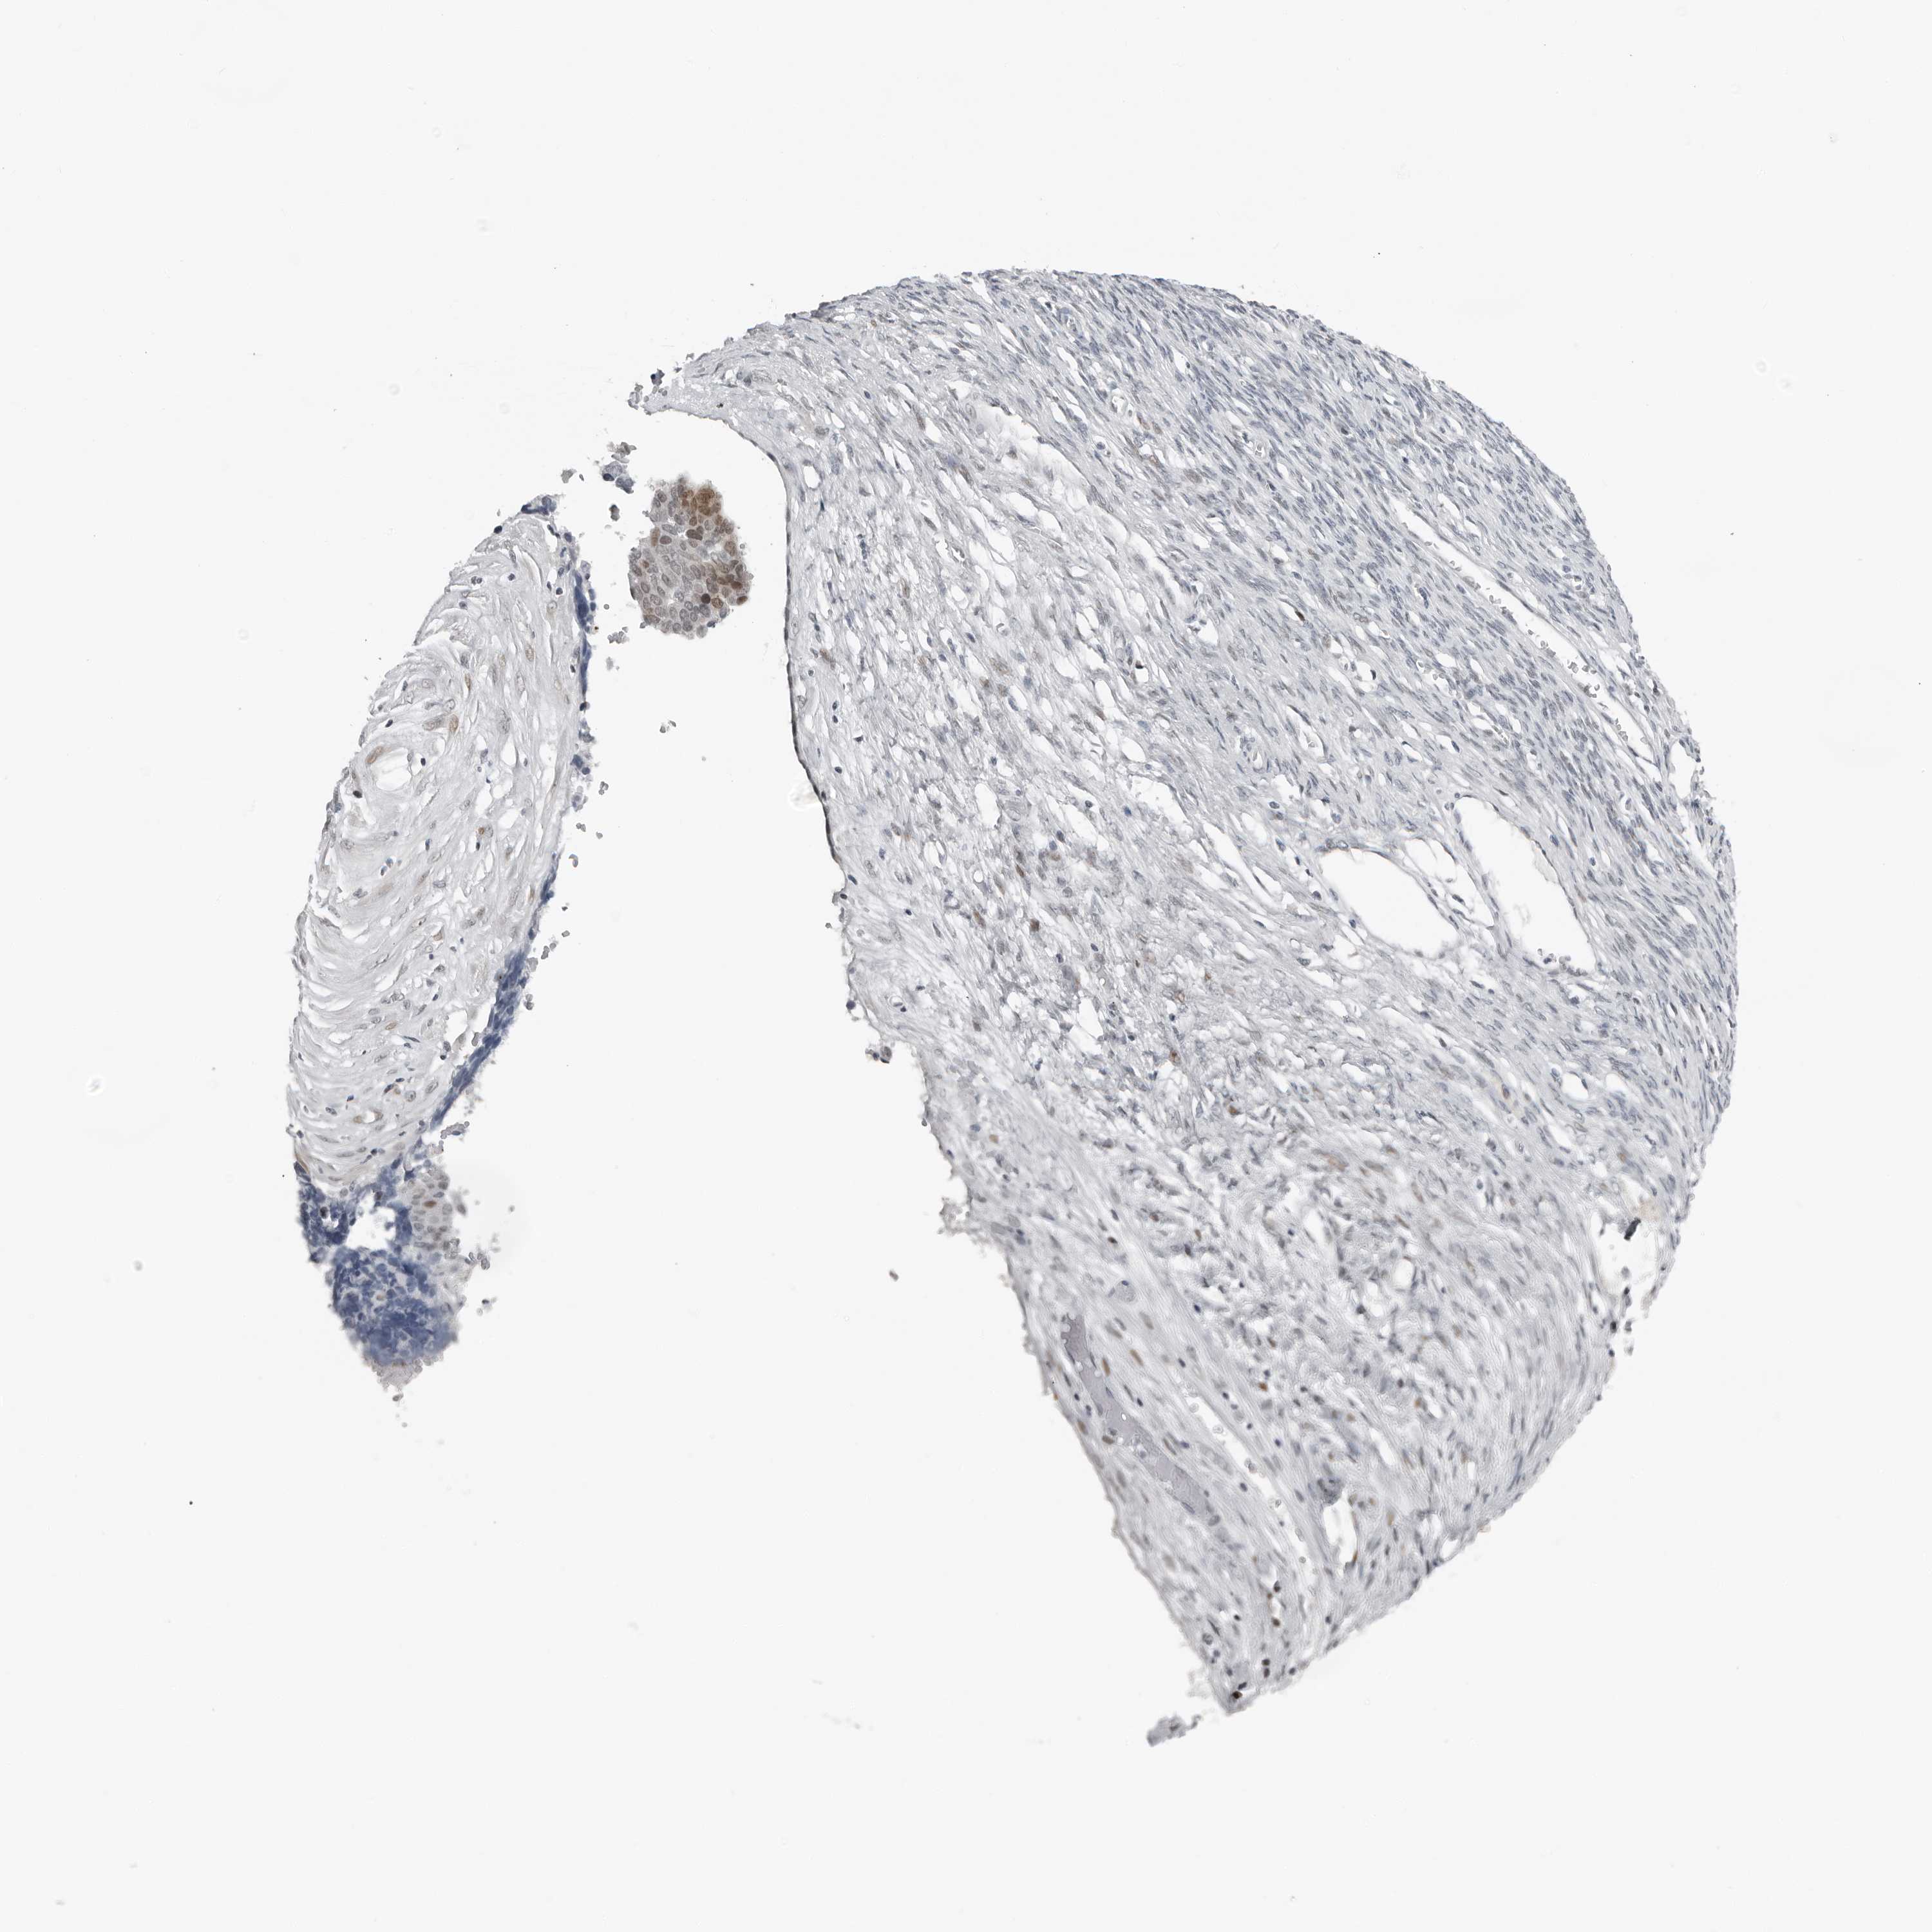

OVARIAN CANCER - Protein expressioni

A mouse-over function shows sample information and annotation data. Click on an image to view it in a full screen mode. Samples can be filtered based on level of antibody staining by selecting one or several of the following categories: high, medium, low and not detected. The assay and annotation is described here.

Note that samples used for immunohistochemistry by the Human Protein Atlas do not correspond to samples in the TCGA dataset.

Antibody stainingi

Antibody staining in the annotated cell types in the current human tissue is reported as not detected, low, medium, or high, based on conventional immunohistochemistry profiling in selected tissues. This score is based on the combination of the staining intensity and fraction of stained cells.

Each image is clickable and will lead to virtual microscopy that enables deeper exploration of all samples and also displays staining intensity scores, fraction scores and subcellular localization as well as patient and tissue information for each sample.

Antibody HPA024313

Antibody HPA027983

Antibody HPA028628

Staining

High

Medium

Low

Not detected

Intensity

Strong

Moderate

Weak

Negative

Quantity

>75%

75%-25%

<25%

None

Location

Nuclear

Cytoplasmic/membranous

Cytoplasmic/membranous,nuclear

Carcinoma, NOS

Cystadenocarcinoma, serous, NOS